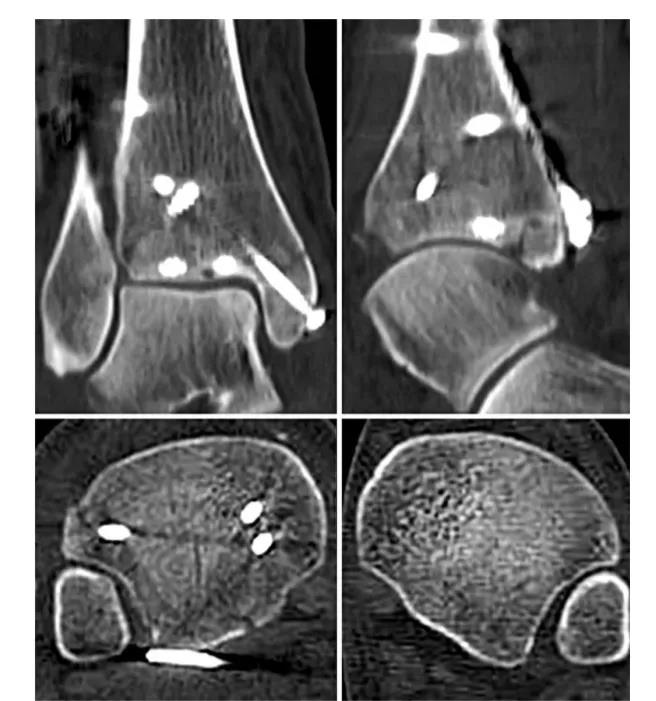

② 四踝骨折典型病例图。

③ 首先俯卧位后外侧入路固定后踝,存在夹层骨块可行克氏针临时固定后抗滑钢板固定后踝。

④ 固定后踝后,经同一后外侧切口固定外踝,通常建议采用后侧钢板固定,如腓骨骨折线过高,则重新切口外侧钢板固定腓骨。⑤ 内踝常规切口固定内踝。⑥ 俯卧位患者屈曲膝关节,经前外侧切口固定前踝骨折块,通常选用2.7mm或3.5mm螺钉,并使用垫圈。

⑧ 复位后典型病例图。